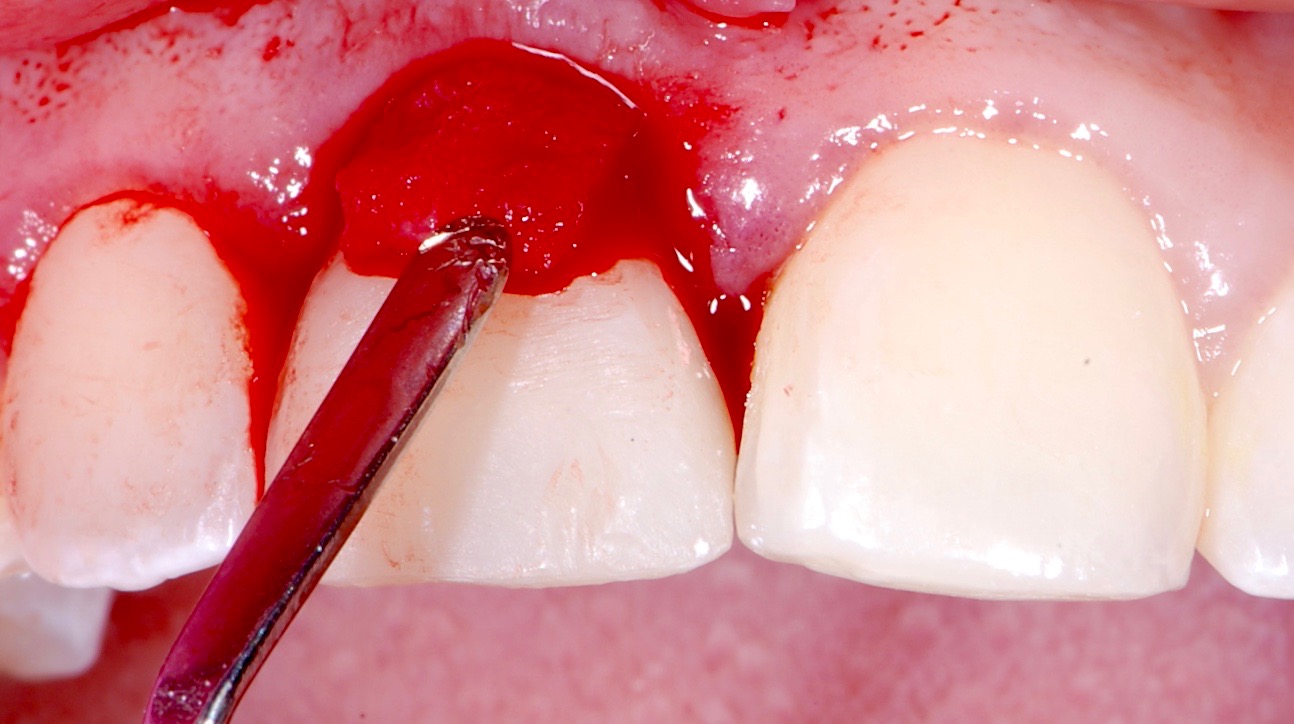

Plugging into digital workflows provides opportunities to integrate CAD/CAM technologies at every step of the treatment process for dental implants. In another example, a patient presented with a failing tooth No. 8 (Figure 6 and Figure 7). After discussing treatment options, the patient chose to forgo any treatment to address tooth and soft-tissue asymmetries and wanted to proceed with a dental implant-supported restoration without additional treatment. After integrated 3-dimensional planning, the tooth was extracted, and then an implant and the final custom CAD/CAM abutment (titanium base with zirconia supra-structure) were placed with a provisional restoration in the same visit (Figure 8 and Figure 9). Soft-tissue grafting was also done at the same visit to address the deficient buccal tissue height on No. 8 (Figure 10). At 3 months, the patient presented for the final restoration, with excellent healing around the implant (Figure 11) and soft-tissue healing guided by the custom abutment (Figure 12).

Fig 10. Placement of an allograft material to address the deficiency of buccal soft tissue. (Implant surgery and soft-tissue grafting performed by David Wong, DDS; Tulsa, Oklahoma.)

Figure 10